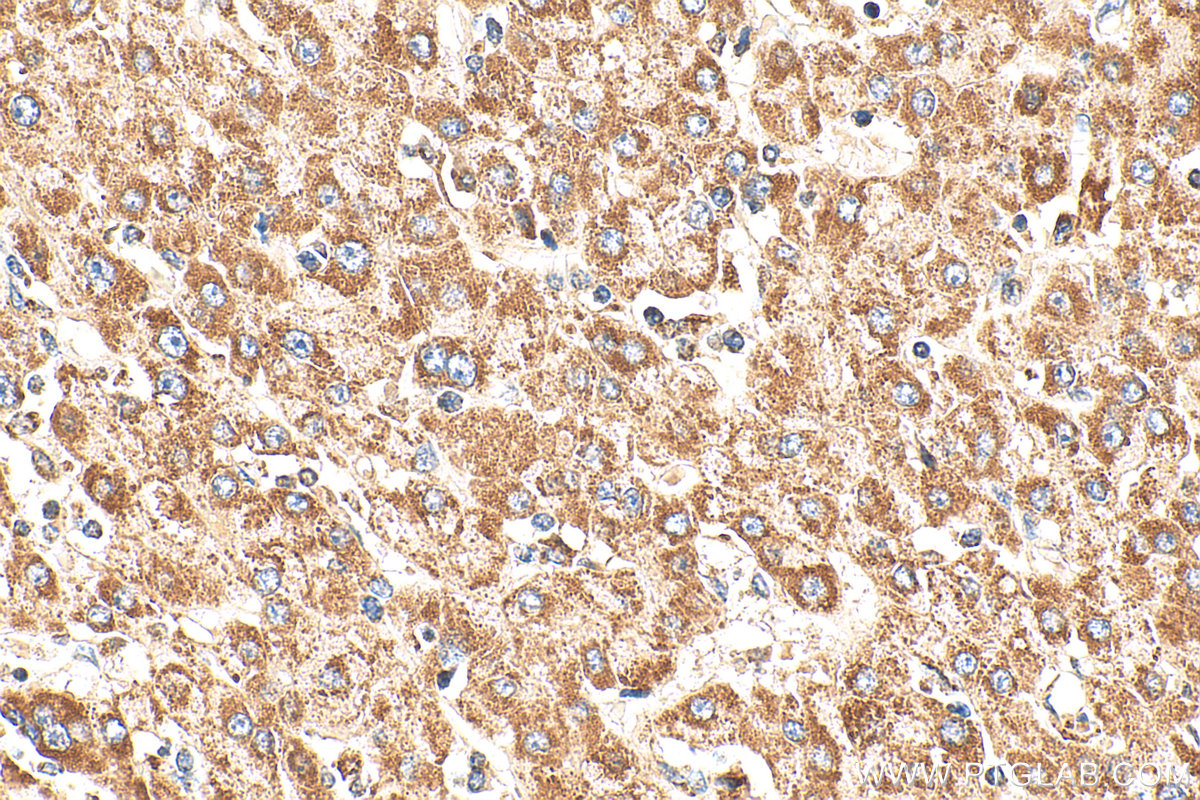

| Positive IHC detected in | human heart tissue, human liver cancer tissue Note: suggested antigen retrieval with TE buffer pH 9.0; (*) Alternatively, antigen retrieval may be performed with citrate buffer pH 6.0 |

| Immunohistochemistry (IHC) | IHC : 1:100-1:400 |